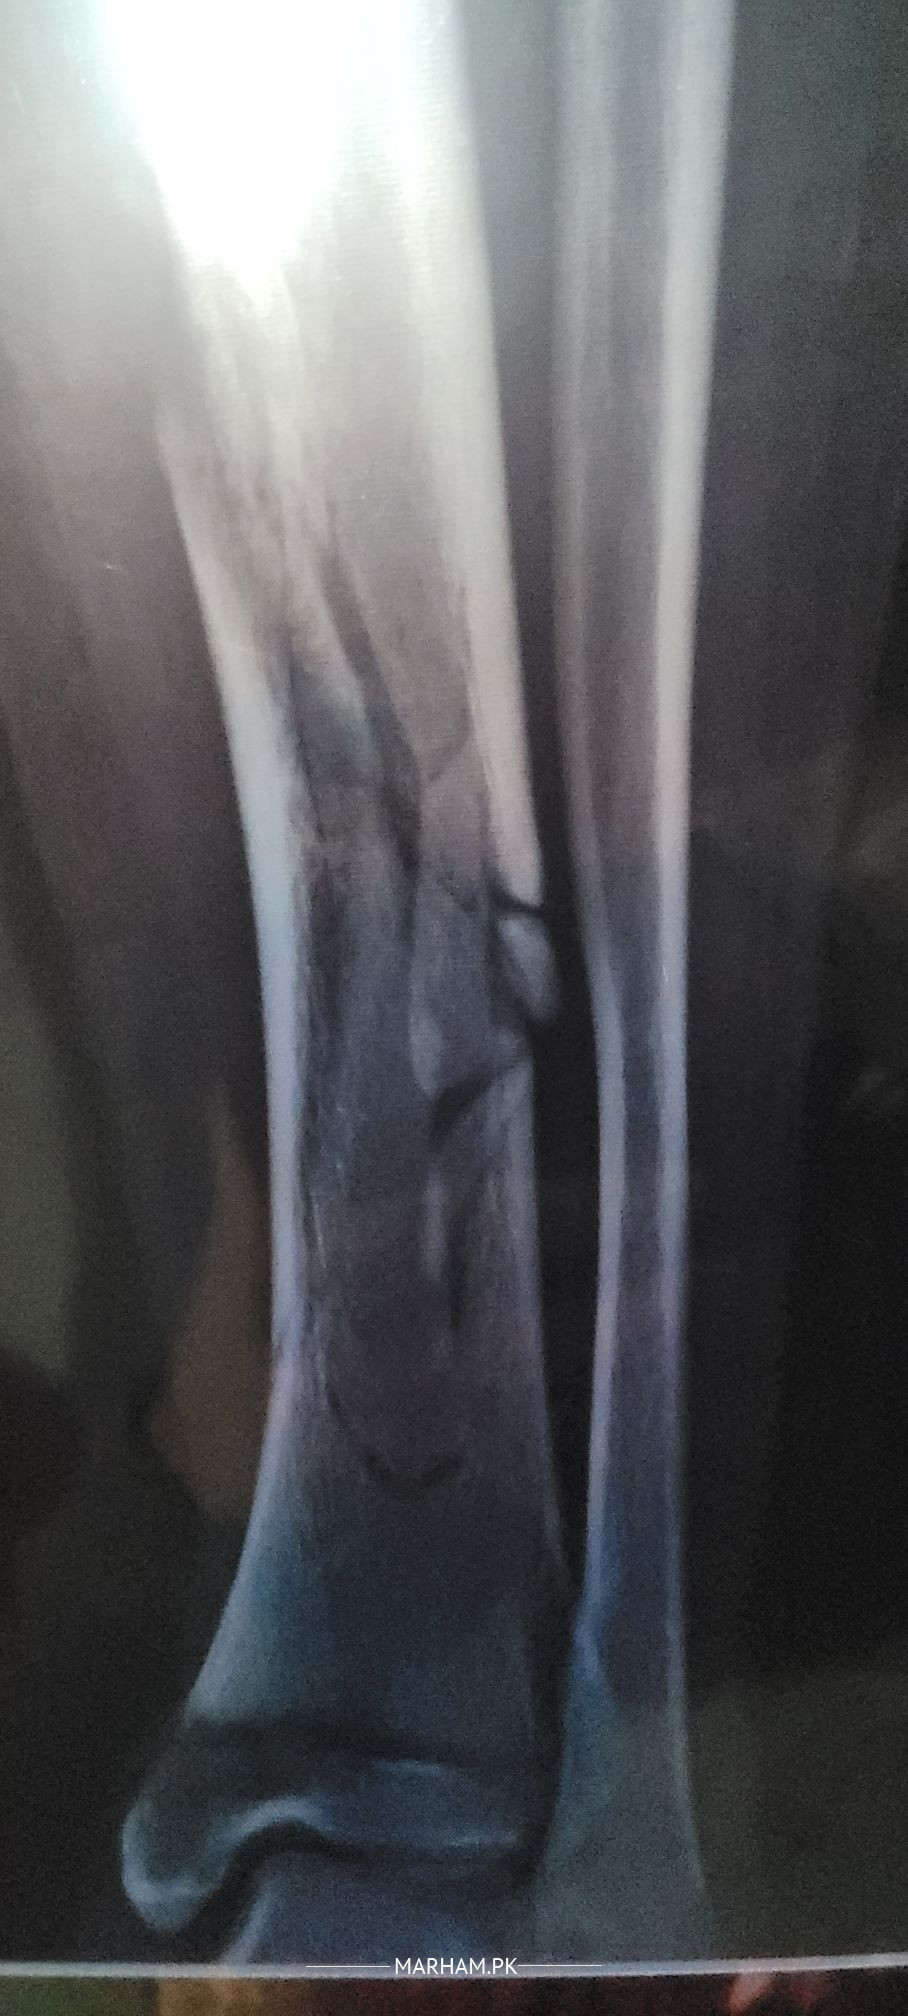

i want to know the bone is straight or not like 19/20 ka difference hai

its a comminuted fracture, heel well with plaster ,alignment is ok

If plan is non operative management, then position is acceptable